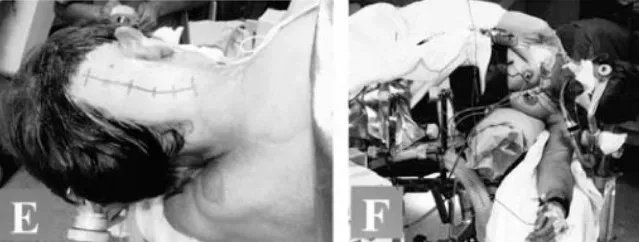

▼手术切口及手术时病人的位置